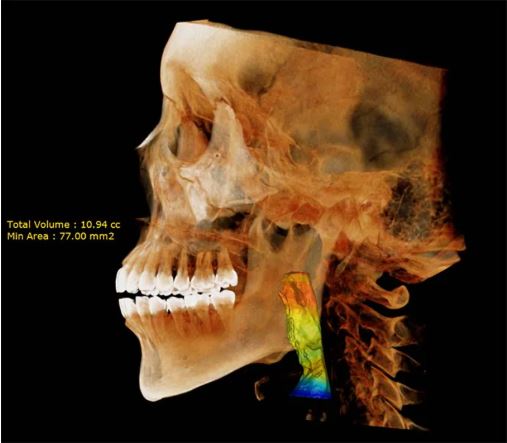

• 3D CBCT Imaging

• Capture highly detailed 3D scans with a maximum FOV of 18 x 16.5 cm—ideal for full dentition, sinus evaluations, TMJ diagnostics, and comprehensive airway assessments, benefiting both dental and ENT professionals.